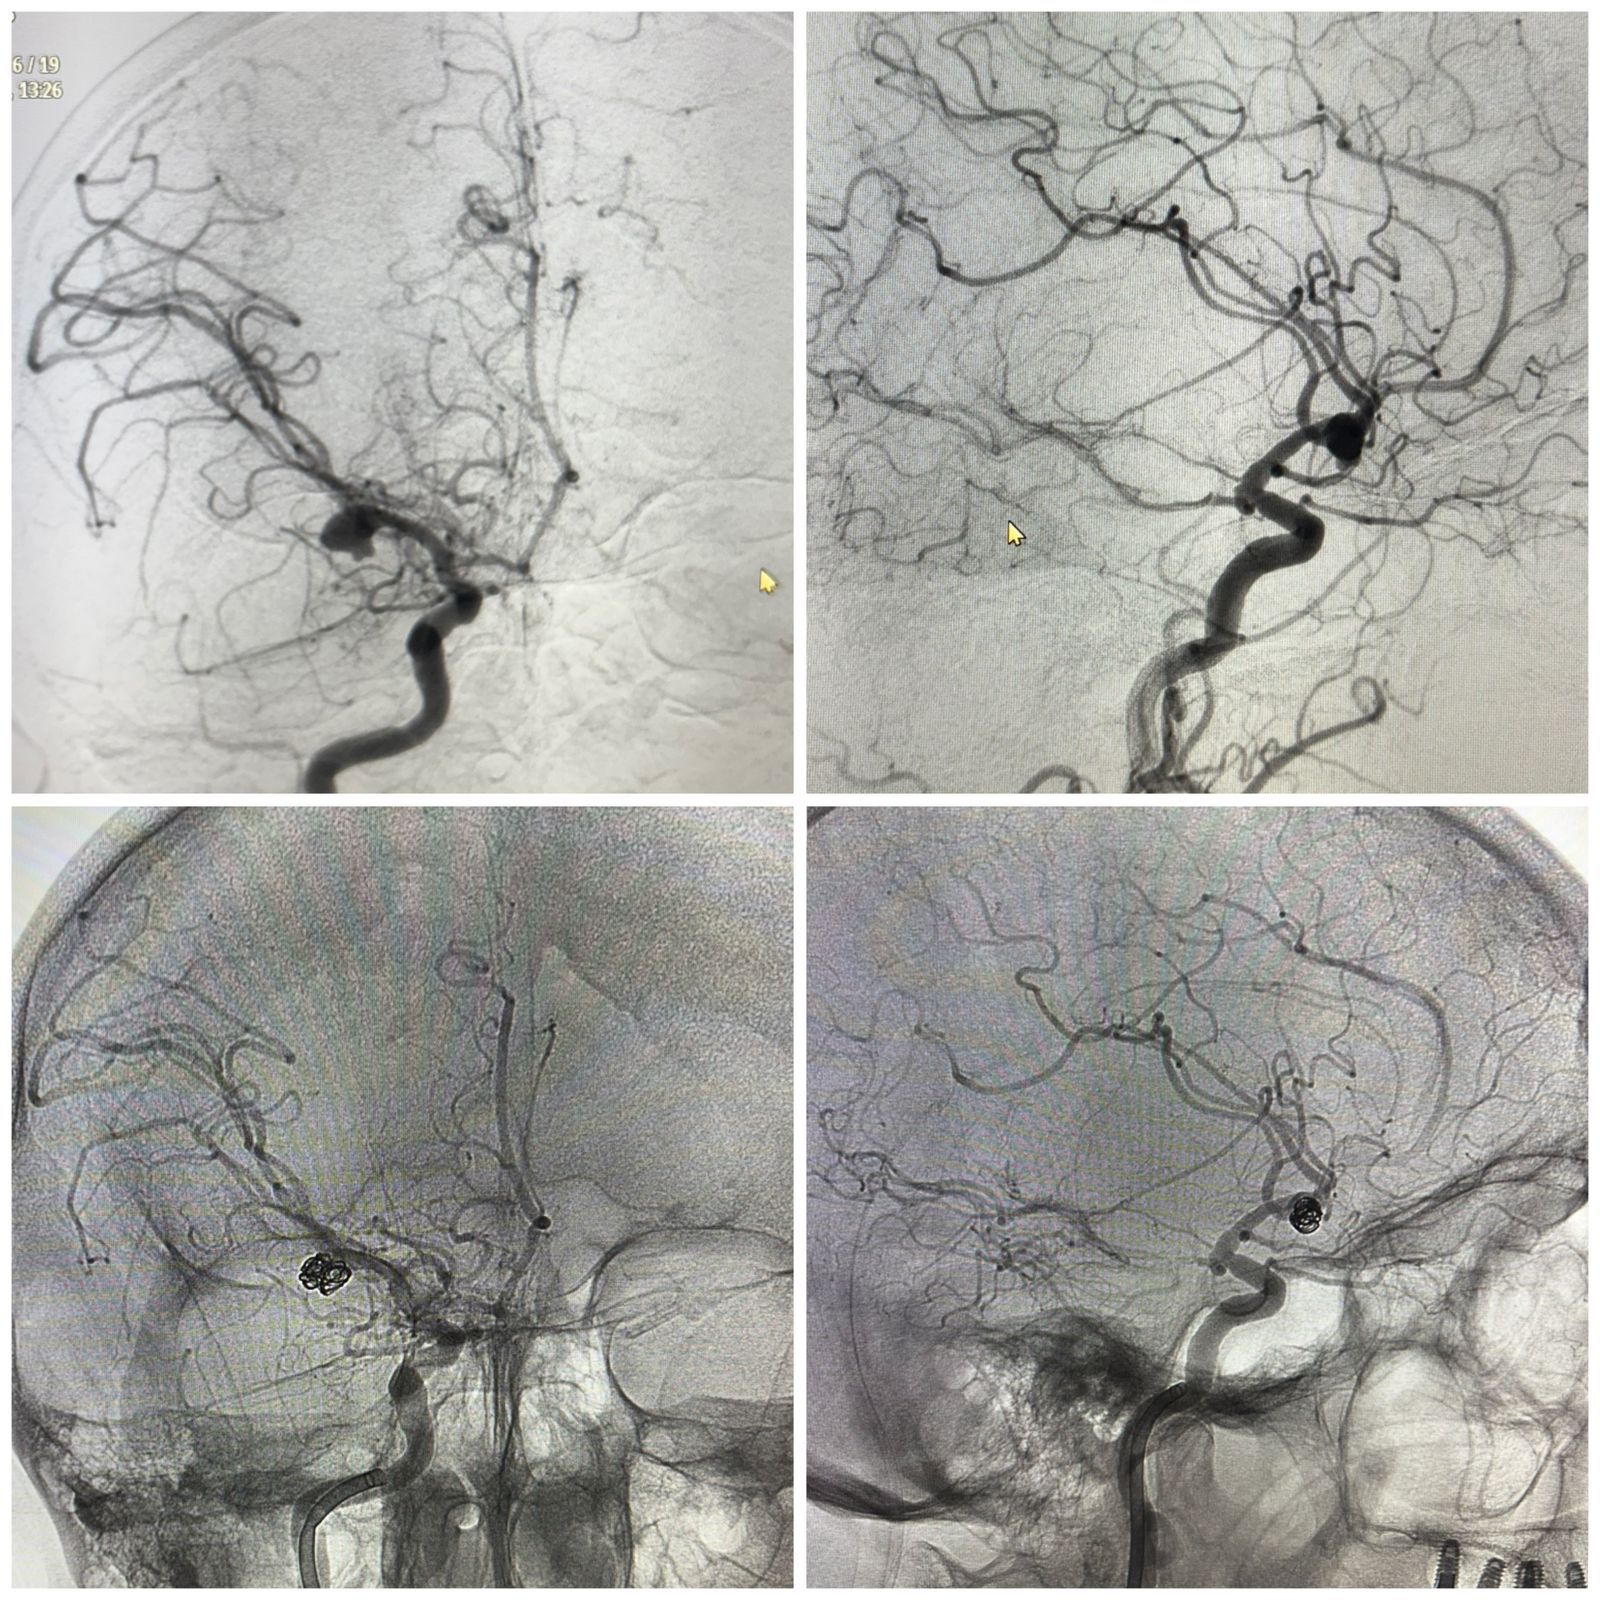

مۇنداي وقيعالاردىڭ باسىم بولىگى ناۋقاس ءتىپتى اۋرۋحاناعا جەتپەي جاتىپ, قايعىلى اياقتالادى. الايدا بۇل جولى ءار مينۋت شەشۋشى ءرول اتقارعان. پاتسيەنتتى مۋلتيديستسيپلينارلىق توپ-نەۆرولوگ, رەانيماتولوگ, نەيروحيرۋرگتەر مەن انەستەزيولوگ ماماندار بىرلەسىپ قابىلدادى. كت-دان باستاپ انگيوگرافياعا دەيىنگى ءاربىر تەكسەرۋ كەزەڭى ءبولىم مەڭگەرۋشىلەرى مەن №4 قكا ينسۋلت ورتالىعى باسشىلىعىنىڭ قاتىسۋىمەن وتكەن كونسيليۋمدا تالقىلانىپ وتىردى.

«مي قۇرىلىمدارىنىڭ قىسىلۋ قاۋپى اسا جوعارى بولعانىن ەسكەرە وتىرىپ, پاتسيەنتكە ءۇش وتانى قاتارىنان جاساۋ قاجەت بولدى. ءبىرىنشىسى – جارىلعان انەۆريزمانى ەندوۆاسكۋليارلىق ەمبوليزاتسيالاۋ. بۇل – قاندى توقتاتىپ, قايتا جارىلۋدىڭ الدىن الۋعا مۇمكىندىك بەرەتىن زاقىمى از نەيروحيرۋرگيالىق ءادىس. ەكىنشىسى – سىرتقى قارىنشالىق درەناج ورناتۋ. ونىڭ ماقساتى – باسىشىلىك قىسىمدى تومەندەتىپ, مي ج ۇلىنى سۇيىقتىعىنىڭ اينالىمىن تۇراقتاندىرۋ. ءۇشىنشىسى – مي ىشىندەگى گەماتومانى الىپ تاستايتىن دەكومپرەسسيالىق وتا. بۇل اسا ءدال ميكروسكوپيالىق تەحنيكانى قاجەت ەتەتىن كولەمدى نەيروحيرۋرگيالىق ارالاسۋ», دەيدى الماتى №4 قالالىق كلينيكالىق اۋرۋحانا نەيروحيرۋرگى الدونگار ايساۋتوۆ.